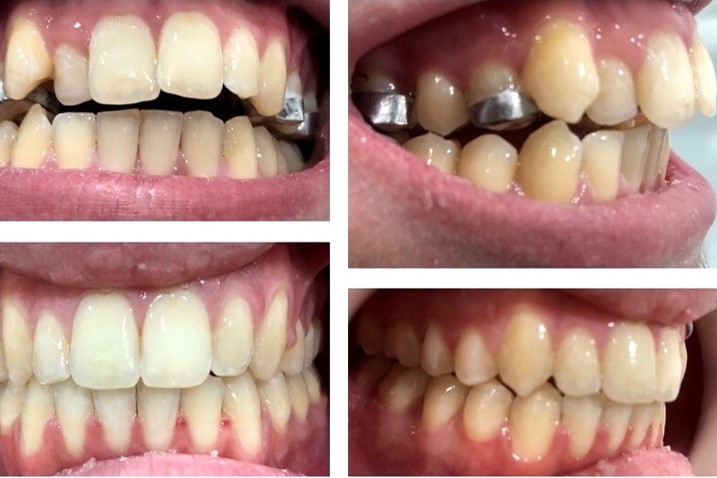

ORTODONTIA

Após uma avaliação rigorosa, prevenimos e corrigimos desarmonias dento faciais em crianças e adultos, permitindo o correto desenvolvimento maxilar e mandibular.

Hoje qualquer má oclusão é tratada facilmente com técnicas fixas ou removíveis..

PRÓTESES

Dispomos de especialistas em reabilitação oral estética, com o objetivo de reproduzir a sua dentição natural, através de próteses fixas (coroas, pontes e facetas dentárias) ou removíveis (esqueléticas ou acrílicas, totais ou parciais).